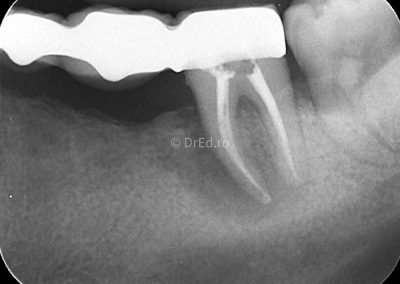

Galerie

Toate imaginile, fotografiile și radiografiile publicate pe acest site sunt protejate prin drepturi de autor și constituie proprietatea exclusivă a Dred.ro.

Aceste materiale sunt furnizate exclusiv în scop informativ și educațional și nu conțin date cu caracter personal sau informații care permit identificarea pacienților, în concordanță cu legislația privind protecția datelor cu caracter personal și GDPR.

Reproducerea, copierea, distribuirea, publicarea, transmiterea, modificarea sau orice altă utilizare, integrală ori parțială, a acestor materiale, în orice formă și prin orice mijloace, fără consimțământul prealabil scris al titularului drepturilor, este strict interzisă și poate atrage răspunderea civilă și/sau penală, în condițiile legii aplicabile privind drepturile de autor și protecția proprietății intelectuale.